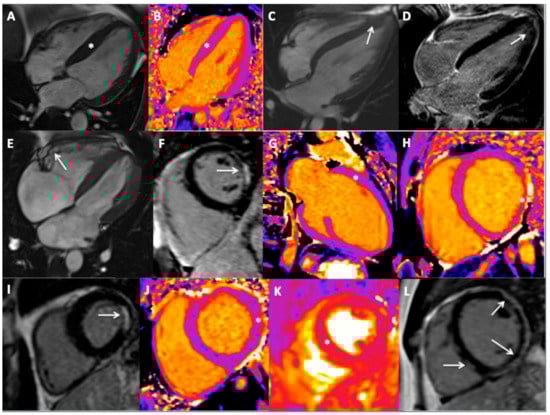

3.2. CMR Findings

3.3. Athlete’s Heart and CMR Result

| LGE in junction point | 13 (22) | 9 (9) | 0.03 |

| LGE other than junction point (n,%) | 11 (19) | 30 (32) | 0.09 |

| ischemic | 1 (2) | 5 (5) | 0.41 |

| non-ischemic | 10 (17) | 25 (27) | 0.25 |

| CMR result | |||

| Disease (n,%) | 19 (32) | 47 (49) | 0.05 |

| Type of disease (n, %) | |||

| HCM | 1 (2) | 10 (11) | 0.05 |

| HCM apical | 2 (3) | 4 (4) | 1.00 |

| All HCM | 3 (5) | 14 (15) | 0.22 |

| DCM | 3 (5) | 3 (3) | 0.68 |

| AC | 1 (2) | 3 (3) | 1.00 |

| LVNC | 0 (0) | 0 (0) | - |

| All cardiomyopathy | 7 (12) | 20 (21) | 0.21 |

| Prior MI | 0 (0) | 6 (6) | 0.08 |

| Acute/prior myocarditis | 7 (12) | 14 (14) | 0.79 |

| Other findings * | 5 (8) | 7 (7) | 0.95 |